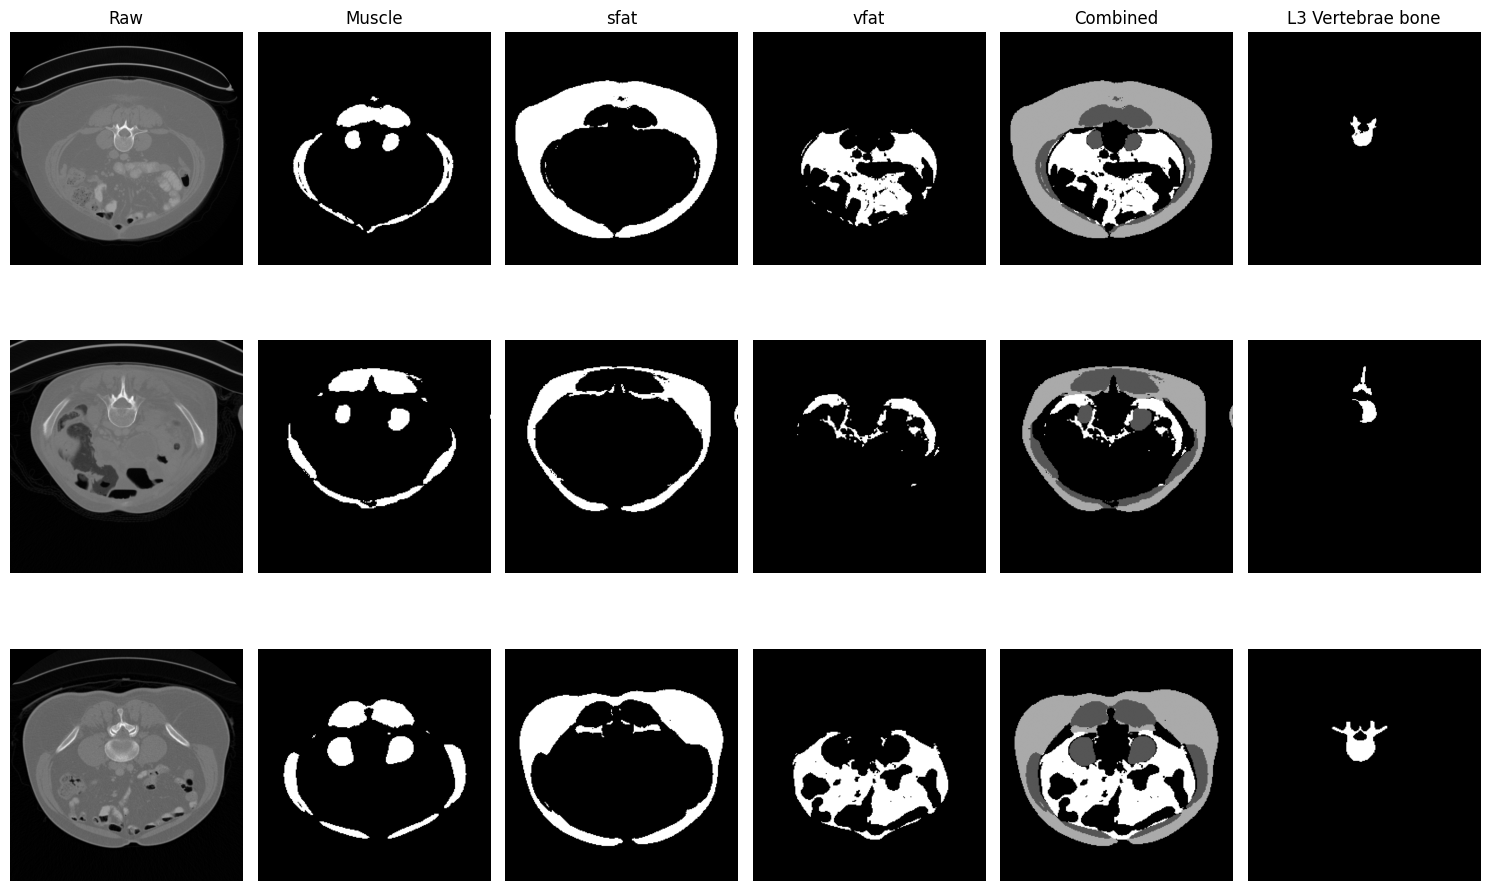

This project presents a deep learning based pipeline for automatic sarcopenia assessment using abdominal CT scans. The system identifies the L3 vertebra slice, segments key body composition structures, and computes clinically relevant metrics used for sarcopenia screening.

Developed an Automated Tool for Sarcopenia Detection. An end-to-end pipeline that locates the L3 slice from the CT volume, extracts, and calculates body compositions to analyze sarcopenia. Co-authored research report “Data Governance - Ethical, Social, Cultural, and Environmental Challenges in Synthetic Media.”